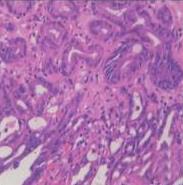

• 色素内镜和窄带成像技术联合放大内镜对早期结直肠癌及癌前病变的诊断价值研究

2026, 32(1):35-41. DOI: 10.12235/E20250020

摘要 (92) HTML (29) PDF 5.33 M (93) 评论 (0) 收藏

摘要:目的 探究色素内镜(CE)和窄带成像技术(NBI)联合放大内镜(ME)对早期结直肠癌及癌前病变的诊断价值研究。方法 选取2023年8月-2024年7月于该院接受检查的疑似早期结直肠癌及癌前病变的患者160例。采用四格表法,分析NBI-ME和CE-ME检测早期结直肠癌及癌前病变的敏感度、特异度和准确度;采用Kappa一致性检验,分析CE-ME和NBI-ME诊断早期结直肠癌及癌前病变与病理检查的一致性。结果 病理结果显示,良性病变52例,癌前病变90例,结直肠癌18例。CE-ME检测结果显示,良性病变43例,癌前病变101例,结直肠癌16例,漏诊率为33.33%;CE-ME诊断早期结直肠癌及癌前病变与病理检查的一致性中度(Kappa = 0.605,P < 0.01),敏感度为66.67%,特异度为97.18%,准确度为93.75%。NBI-ME检查结果显示,良性病变43例,癌前病变100例,结直肠癌17例,漏诊率为16.67%,NBI-ME诊断早期结直肠癌及癌前病变与病理检查的一致性较高(Kappa = 0.714,P < 0.01),敏感度为88.33%,特异度为98.59%,准确度为96.88%。CE-ME与NBI-ME两者联合检查结果显示,良性病变56例,癌前病变86例,结直肠癌18例,漏诊率为5.56%,两者联合诊断早期结直肠癌及癌前病变与病理检查的一致性极高(Kappa = 0.857,P < 0.01),敏感度为94.44%,特异度为99.30%,准确度为98.75%,高于CE-ME和NBI-ME单独检查。结论 CE和NBI联合ME对早期结直肠癌及癌前病变具有较高的诊断价值。值得应用于临床。